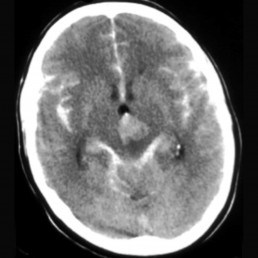

Many aneurysms are diagnosed when they bleed. Most aneurysms are located on arteries that surround the brain in a compartment called the subarchnoid space. When these aneurysms rupture the bleeding is around the brain, called a subarchnoid haemorrhage. The classical symptom is a sudden agonizing headache, sometimes with a transient loss of consciousness. The diagnosis of an aneurysmal subarachnoid haemorrhage is made by a CT scan.

CT Head with extensive subarachnoid haemorrhage: